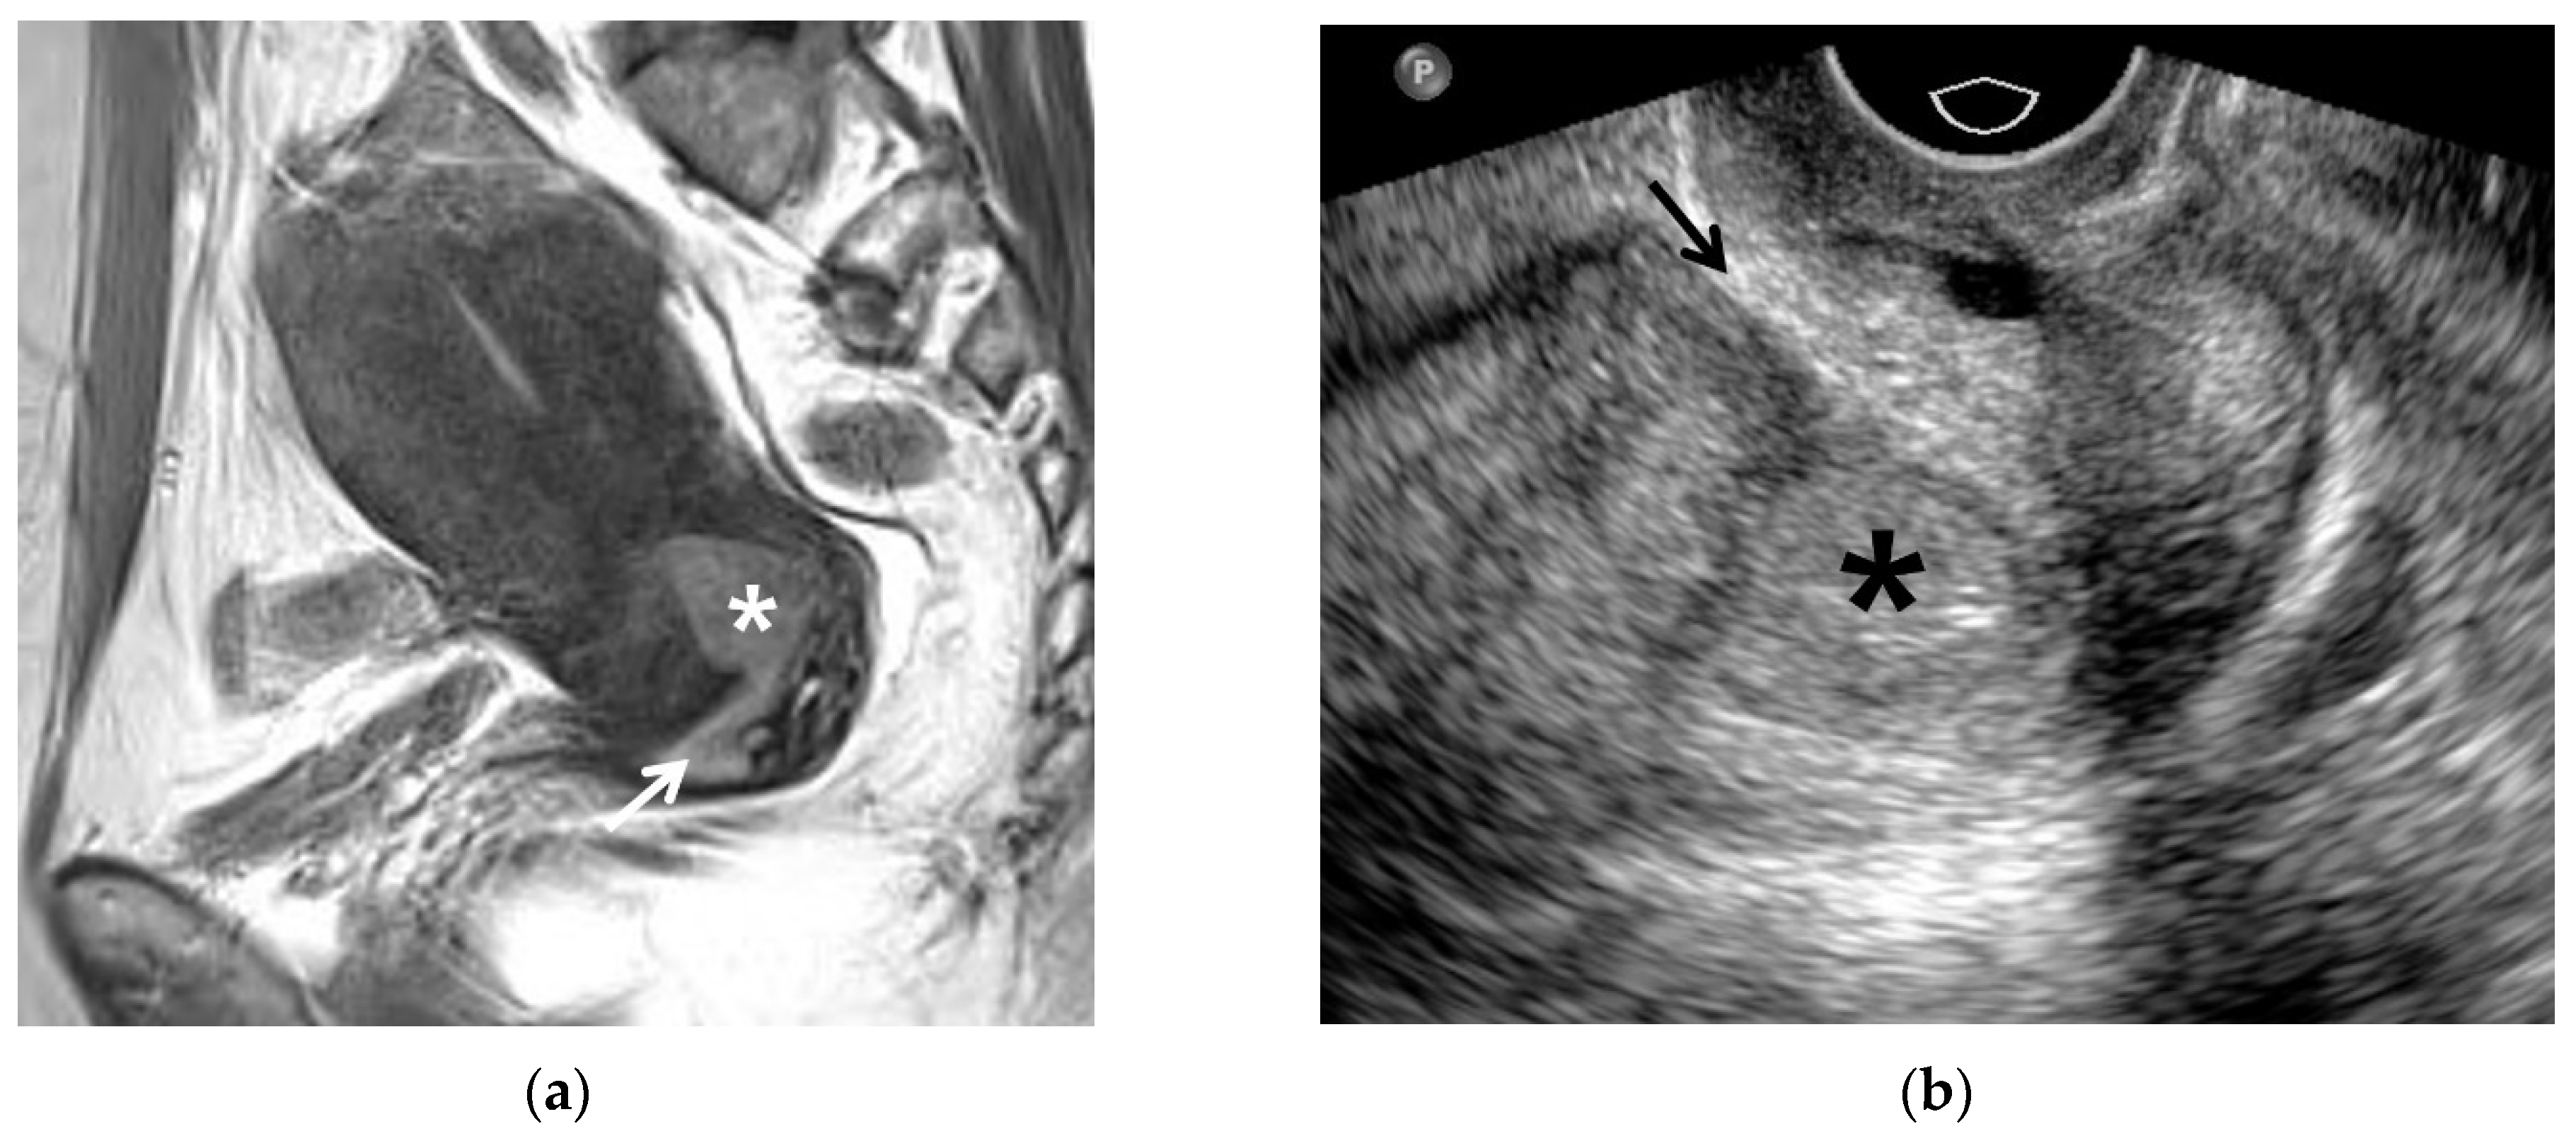

7. Early Detection of Recurrent Cancer

8. Lymph Node Metastasis